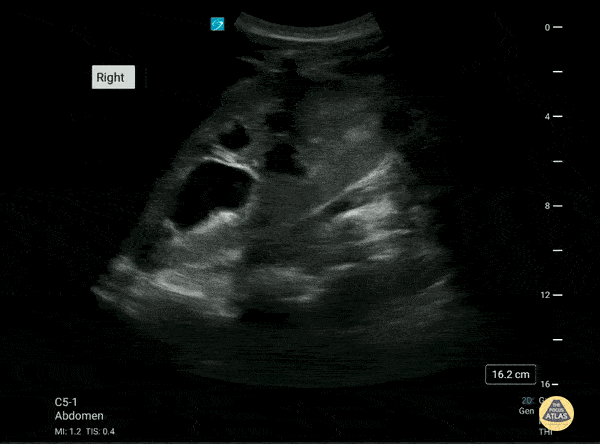

Renal/GU - Moderate-Severe Hydronephrosis

This is the right renal ultrasound of a 20 year old male with a past medical history of recurrent obstructing nephrolithiasis. There is a moderate to severe hydronephrosis present. with what appears to be some thinning of the renal cortex. Brittany Ladson, DO; Sara Schumbach, MD